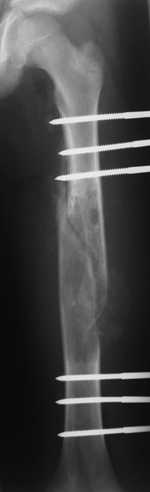

Re: Pathological fracture femur

Most likely fibrous dysplasia, we had the same case but younger age patient 4 years ago treated by uniplanar ext fix followed by percut. curretage and bone marrow injection and healed well.

at this age IMN can solve the problem .

Dear colleagues, I completely agree with Dr. Freih Odeh Abu Hassan. I am not sure about ImN at this case but, in my opinion, ExFix, curretage and bone marrow injection is one of the best decision.

I agree that this case is fibrous dysplasia.

As a method of treetment I propose removal of fibous tissue and cavity allografting, including frozen cortical long graft as an intramedullary nailing. I think it is a good decision without using of any metal construction.